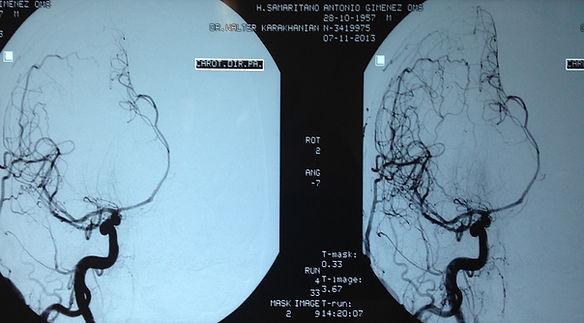

ANGIOGRAFIA CEREBRAL DIGITAL

A angiografia cerebral digital é um exame neurorradiológico de caráter investigativo, e consequentemente diagnóstico, o qual utiliza-se de raios-x para documentar a imagem dos vasos sanguíneos cerebrais, cervicais (região do pescoço), tronco supra aórtico (acima da área cardíaca), etc, com auxílio de um contraste injetado por via arterial na circulação sanguínea, tornando-se visível a imagem das artérias e veias cerebrais, cervicais.

Ao longo das últimas duas décadas, os métodos de imagem vascular cerebral não-invasivos, como o ultrassom-doppler (US doppler), a angiografia por tomografia computadorizada (angioTC), e a angiografia por ressonância magnética (angioRNM) tornaram-se cada vez mais disponíveis. Devido à melhora da resolução espacial, de tempo, e a reconstrução em 3 dimensões desses exames, o papel da angiografia cerebral digital com subtração, mais invasiva tem sido mais restrito, tendo suas razões conforme orientação do neurocirurgião em situações que se façam necessárias como condutas de embolização para aneurismas cerebrais, definição diagnóstica de um aneurisma cerebral, ou malformações artério-venosas intracranianas.

Apesar de ser considerado um procedimento diagnóstico invasivo, ele é relativamente seguro, e envolve o cateterismo arterial carotídeo e vertebral e, portanto, e com um pequeno risco de complicações neurológicas graves. A angiografia cerebral continua sendo o padrão ouro para o estudo dessas doenças intracranianas, e deve ser realizada no primeiro momento disponível quando um paciente é diagnosticado com uma hemorragia subaracnóide não traumática. O estudo angiográfico cerebral tem grande validade também em tumores cerebrais vascularizados.

A Angiografia Cerebral Digital consiste em um exame neurorradiológico, no qual é realizada uma punção na região inguinal / femural, e com auxílio de catéteres de diferentes formatos, e de um fio guia com o objetivo de avaliar a circulação intracraniana com a visualização dos vasos cerebrais intracranianos do chamado polígono de Willis, com auxílio de uso de contraste não iônico, e de radiação ionizante (raio-x). Eventualmente pode-se realizar o exame pela via braquial ou radial (sistema arterial no braço-antebraço) em casos em que o acesso por via femoral não é possível (p.ex: existência de uma oclusão) ou quando não é possível a cateterização de algum vaso como a artéria femoral (ref: Netter). Abaixo figura demonstratativa da realização do exame de angiografia cerebral.

A circulação arterial intracraniana é subdividida em um sistema anterior e um posterior. O sistema anterior é composto principalmente pelas artérias cerebrais anterior e média, ramos da artéria carótida interna, que por sua vez é ramo da carótida primitiva, oriunda esta do tronco braquiocefálico à direita. A circulação arterial posterior é constituída do tronco basilar sendo seus ramos mais importantes as artérias cerebelares e cerebrais posteriores. O tronco basilar provém da fusão da artéria vertebral direita e esquerda ao nível do sulco ponto-bulbar, ressaltando-se que as artérias cerebelares póstero-inferiores se originam do segmento terminal das artérias vertebrais.

As principais indicações de angiografia cerebral são: malformações arterio-venosa, aneurisma cerebral, vasculite, estenose intracraniana, estenose carotídea e vertebrais nos acidentes vasculares encefálicos isquêmicos, tumores cerebrais, hemorragias intracerebrais, trombose venosa cerebral, etc.

A realização da angiografia cerebral digital tem especial indicação no diagnóstico da hemorragia meníngea ou subaracnóide. O estudo angiográfico cerebral permite a análise detalhada de aneurismas cerebrais. Devido ao alto risco de ressangramento nas primeiras 24 horas, a angiografia precoce permite uma maior agilidade na decisão terapêutica e no prognóstico do paciente.

Angiografia cerebral demonstrando desvio da artéria cerebral anterior por um tumor intracraniano=meningeoma.

Imagem de aneurisma cerebral -Imagem de tratamento do aneurisma tratado pro embolização -método utilizando-se a angiografia cerebral por cateterismo femural.